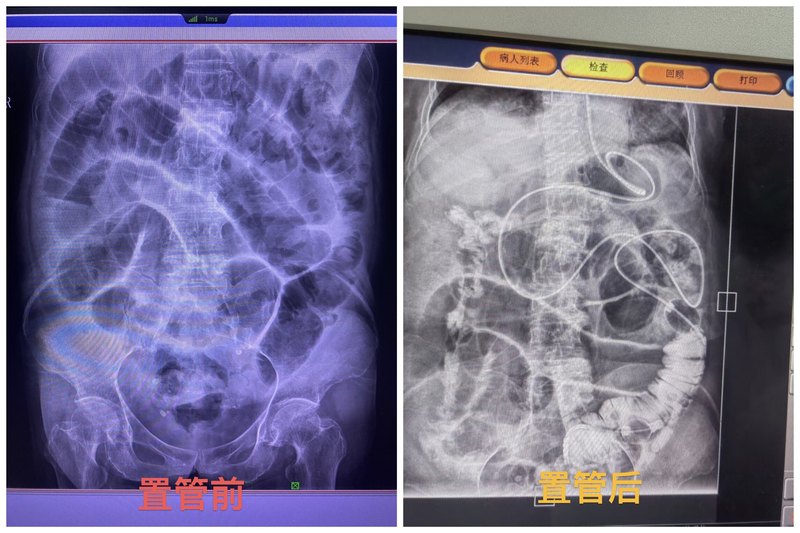

高效減壓 · 精準(zhǔn)守護(hù)

腸梗阻是臨床常見疾病,常表現(xiàn)為腹痛、腹脹、嘔吐、肛門停止排氣排便。若未及時(shí)解除梗阻,可能引發(fā)一系列嚴(yán)重并發(fā)癥:如腸壁缺血壞死、腸穿孔、感染性休克、循環(huán)衰竭,甚至危及生命。近期我們通過小腸減壓為復(fù)雜性腸梗阻的患者帶來了新生,成功讓患者“吃、喝、拉、撒”皆無憂。小腸減壓管不同于傳統(tǒng)的胃管,長約3米,可深入空腸甚至回腸,沿導(dǎo)管全長分布多個(gè)側(cè)孔,可引流多段腸腔內(nèi)容物,通過管道將腸道內(nèi)的氣體和液體排出,降低腸道壓力,改善腸道功能,促進(jìn)腸道恢復(fù),減輕患者痛苦。一根細(xì)管,三米柔腸,探入幽深的迷宮,穿越腫脹的戰(zhàn)場。金屬頭輕叩梗阻的枷鎖,側(cè)孔如星,點(diǎn)亮淤塞的汪洋。負(fù)壓輕啟,引流的詩行在腹腔流淌,脹痛消散,腸鳴重生,這是最溫柔的破曉之光。江西省中醫(yī)院為您“腸”守健康。